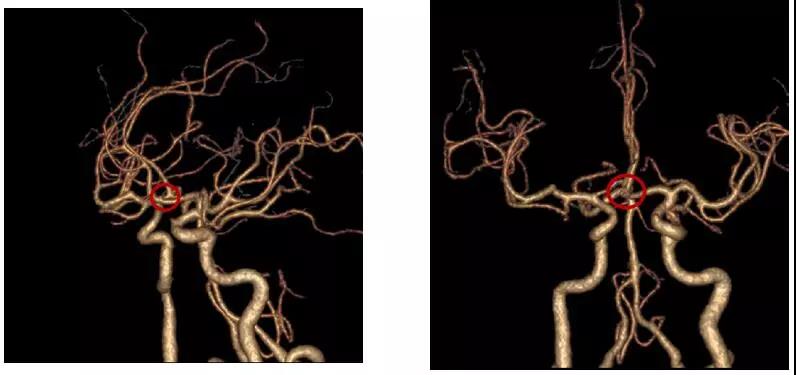

今年52歲的賴先生在外院檢查發(fā)現(xiàn)顱內(nèi)動脈瘤1周,為求進一步治療前來惠州三院,頭顱CTA檢查提示:前交通動脈瘤?;颊呒韧刑悄虿?年和高血壓1年病史,未進行正規(guī)治療和監(jiān)測。

患者術(shù)前頭部CTA

經(jīng)過詳細地病情評估及術(shù)前討論,李雪松醫(yī)療團隊決定采用眉弓鎖孔入路這項技術(shù),為患者施行手術(shù)。